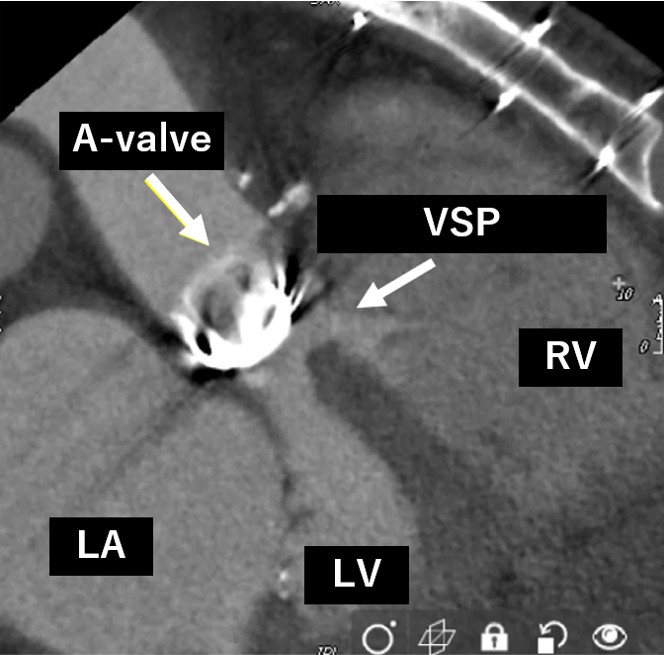

Blood tests showed an increase in totalbilirubin to 5.0 mg/dl, along with an increase in LDH and decreases in Hb andhaptoglobin, indicating hemolytic anemia. NTproBNP also increased to over 3000.The transthoracic echocardiogram showed the VSP at the membranous septum nearthe aortic PVL, and also moderate tricuspid regurgitation. Aortogram and CTscan demonstrated the severe aortic PVL with interventricular left to right shuntnearby.

Our heart team decided to perform both VSP and PVL closure by transcatheter technique because of the previous multiple open-heart surgery with high surgical risk score. Before percutaneous VSP closure, the oximetry-run exams revealed Qp/Qs 1.3 but the transesophageal echo(TEE) showed the EROA of aortic PVL was 0.51 mm2 and the defect size was 10.5 x 5.4 mm which meant severe PVL. We also confirmed the defect size of VSP with TEE, and the size was 8.1mm.